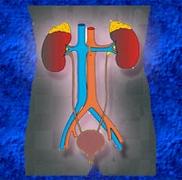

قابلیت تبدیل اورولوژی یزد به عنوان قطب اورولوژی جنوب شرق کشور

مدیر گروه اورولوژی دانشگاه علوم پزشکی یزد گفت: اورولوژی یزد قابلیت تبدیل به عنوان قطب اورولوژی جنوب شرق کشور را داراست. ...